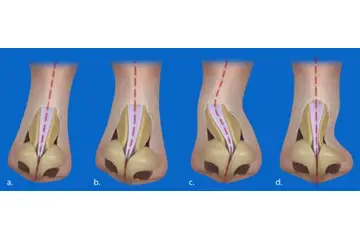

3. Tanı Yöntemleri Diz kıkırdak aşınması tanısı, klinik muayene ve görüntüleme yöntemleri ile konulmaktadır. Bu yöntemler arasında:

4. Tedavi Yöntemleri Diz kıkırdak aşınması tedavisi, hastanın durumuna ve aşınmanın derecesine bağlı olarak değişmektedir. Tedavi yöntemleri şunları içermektedir: